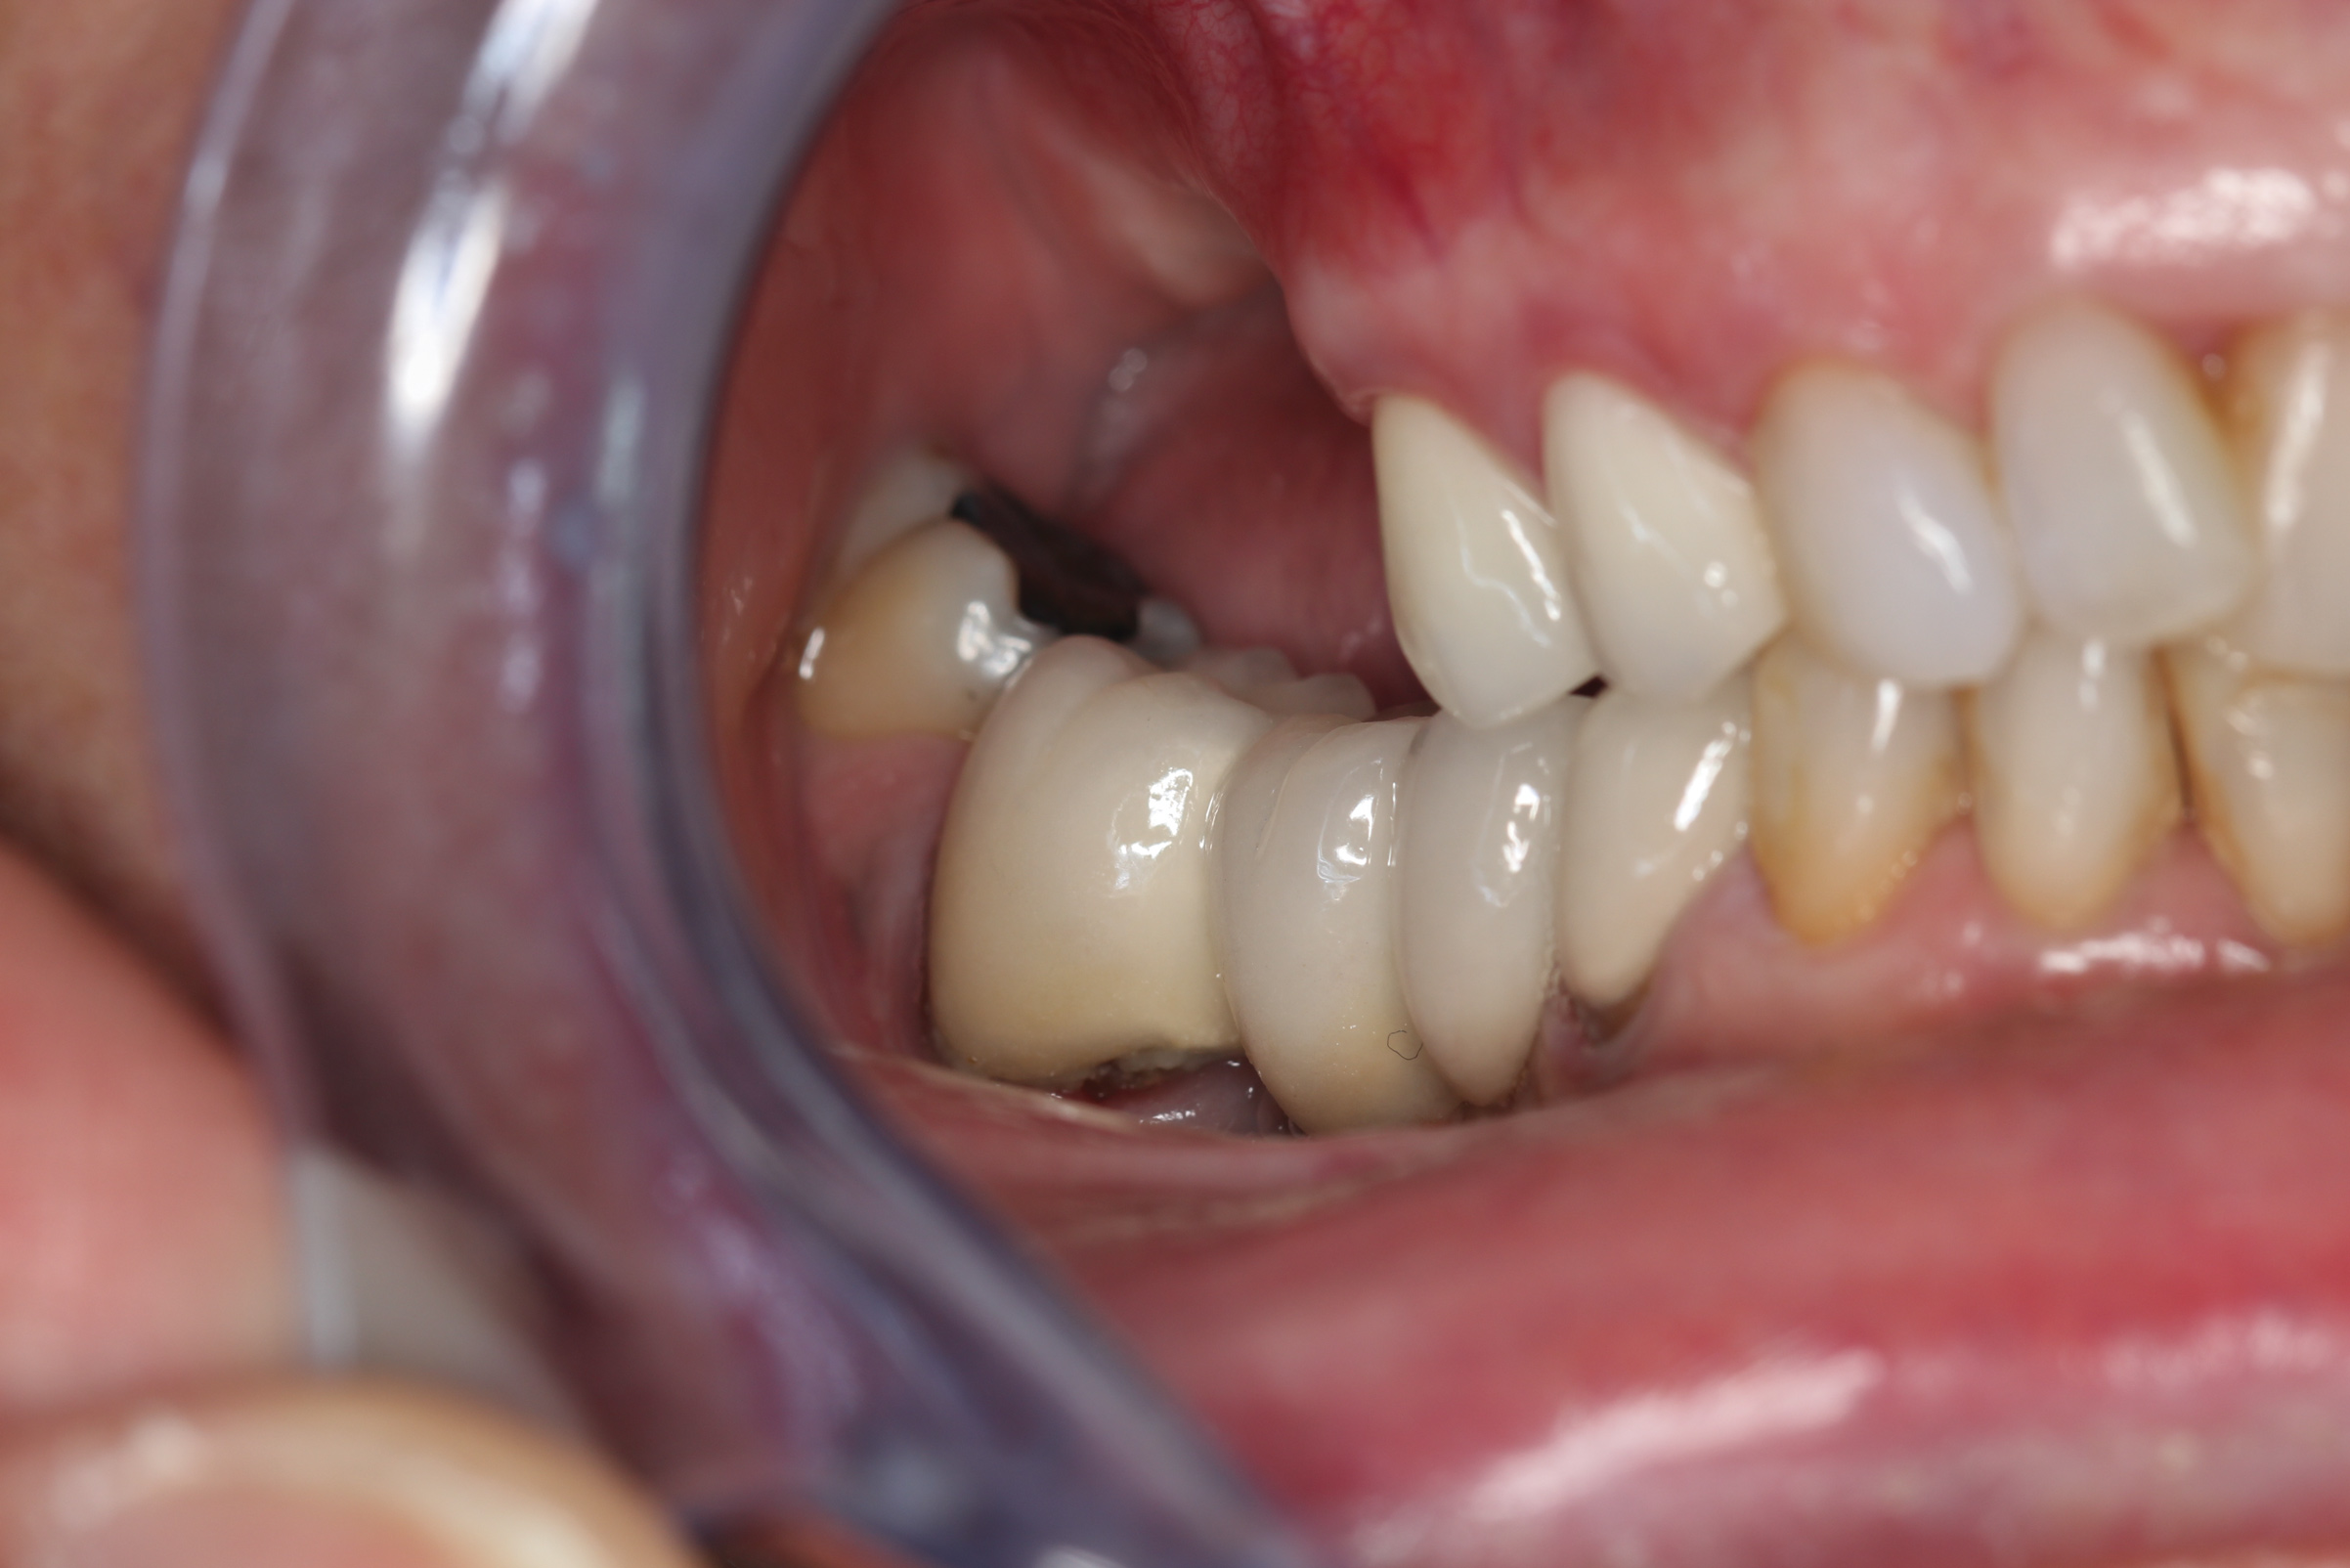

Fig 20. After placement of bone grafting putty in the defect, the implant was inserted. Note the remaining bone grafting putty on the buccal aspect of the implant.

Figure 20

Fig 21. Soft-tissue healing after 3 months. Note maintenance of the facial gingival zenith.

Figure 21

Fig 22. Final restoration after 1.5 years. Note the soft-tissue contour on the buccal aspect.

Figure 22